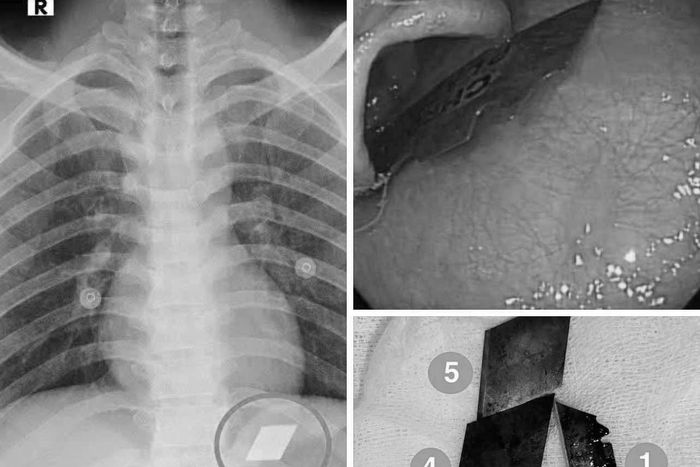

Nam thanh niên vào cấp cứu vì nuốt nhiều mảnh dao rọc giấy, dao lam. Các bác sĩ ngay lập tức nội soi gắp dị vật cho bệnh nhân.

Ngày 10/7, Khoa Hồi sức cấp cứu - Bệnh viện Đa khoa Bình Dương (TPHCM) tiếp nhận một trường hợp hy hữu. Nam bệnh nhân P.V.L (26 tuổi) nhập viện cấp cứu trong tình trạng nuốt nhiều dị vật kim loại sắc nhọn, bao gồm dao rọc giấy và dao lam.

Qua thăm khám và chụp X-quang, các bác sĩ phát hiện dị vật cản quang tại vị trí dạ dày. Bệnh nhân lập tức được chỉ định nội soi cấp cứu. Dưới sự phối hợp chặt chẽ giữa ê-kíp nội soi và gây mê, các bác sĩ đã gắp thành công 4 lưỡi dao rọc giấy ra khỏi dạ dày và một phần lưỡi dao lam mắc tại vùng hạ họng - miệng thực quản.

Hình ảnh dị vật trong đường tiêu hóa. Ảnh: BVCC.